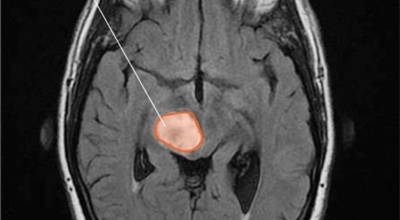

가장 흔한 뇌종양은 수막종이며 종양의 크기나 위치에 따라 수술이 필요하지 않을 수 있지만 청각 신경초종은 이명을 발생시킬 수 있다고 하며 심한 경우 안면 마비, 경련 및 통증을 발생시킬 수 있지만 뇌종양은 생존을 좌우하게되는 교모세포종 문제가 뒤늦게 생기는 것으로 주의가 필요한 이유이예요.